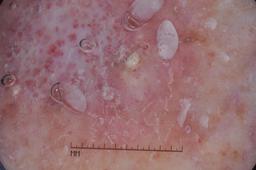

ISIC-DICM-17K (ISIC Dermoscopic Images and Clinical Metadata 17K) is a curated and balanced dataset derived from the International Skin Imaging Collaboration (ISIC) Archive Gallery. It comprises 17,060 dermoscopic images and clinical metadata (8,530 melanoma and 8,530 non-melanoma classes).

For more details, please follow the project’s GitHub repository: https://github.com/mmu-dermatology-research/isic-dicm-17k

This dataset was used in this study and benchmark to explore the effectiveness of multimodal learning for skin lesion classification:

S. Ahammed, X. Cui, W. Lu and M. H. Yap, "Skin Lesion Classification using Dermoscopic Images and Clinical Metadata: Insights from Multimodal Models," 2025 IEEE/CVF Conference on Computer Vision and Pattern Recognition Workshops (CVPRW), Nashville, TN, USA, 2025, pp. 222-230, DOI: 10.1109/CVPRW67362.2025.00027